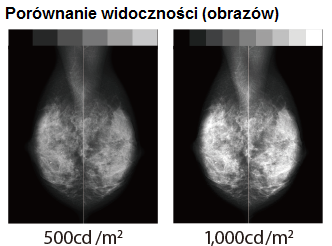

Monitor MS-S500 to następca modelu MS55i2 plus. W porównaniu do swojego poprzednika oferuje on bardzo wysoką jasność maksymalną wynoszącą aż 3000cd/m², gwarantując tym samym bardzo długi czas pracy oraz bardzo wysoki kontrast wyświetlanego obrazu. Jasność po kalibracji wynosząca 1000cd/m² zapewnia ostre i bardzo wyraźne obrazowanie tkanki piersiowej.

Monitor MS-S500 jest fabrycznie kalibrowany do jasności 1000 cd / m2, co czyni go najlepszym rozwiązaniem do ogladania obrazów piersi. Wysoka jasność ekranu monitora radykalnie zwiększa ilość widzianych odcieni szarości, dzięki czemu wykrywalność mikrozwapnień i guzów jest dużo większa.